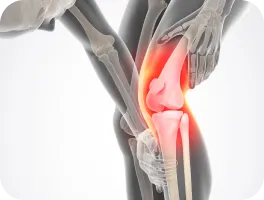

무릎 통증

• 무릎 통증이 있다.